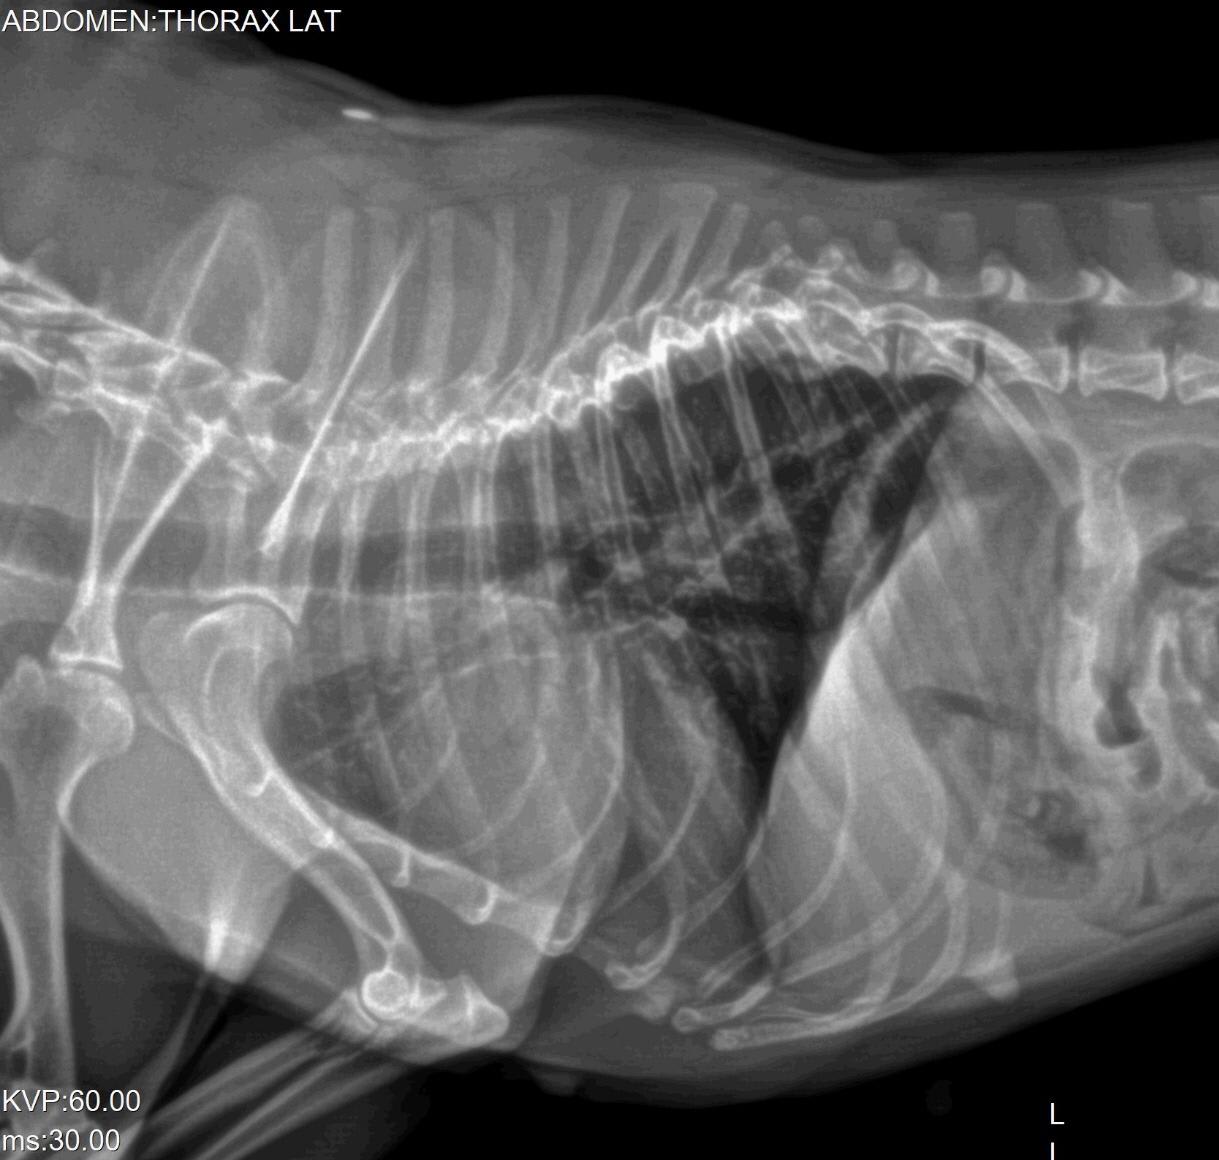

Our 2 year old french bulldog has been shivering from time to time since one week ago. We took her to the vet but want a second opinion. See images attached. We would appreciate your comments.

The hips look ok (hip dysplasia is possible on the right hip joint, but the positioning isn't perfect, which is required for that diagnosis). She does have significant issues with the vertebrae in her thoracic spine. I cannot tell exactly what is going on from these x-rays (it is much easier to evaluate them in-person), but they are likely causing significant discomfort. Lulu may need pain medications for life. A second opinion from a veterinary orthopedic surgeon would be a good idea to see if there is a surgical option to provide pain relief.